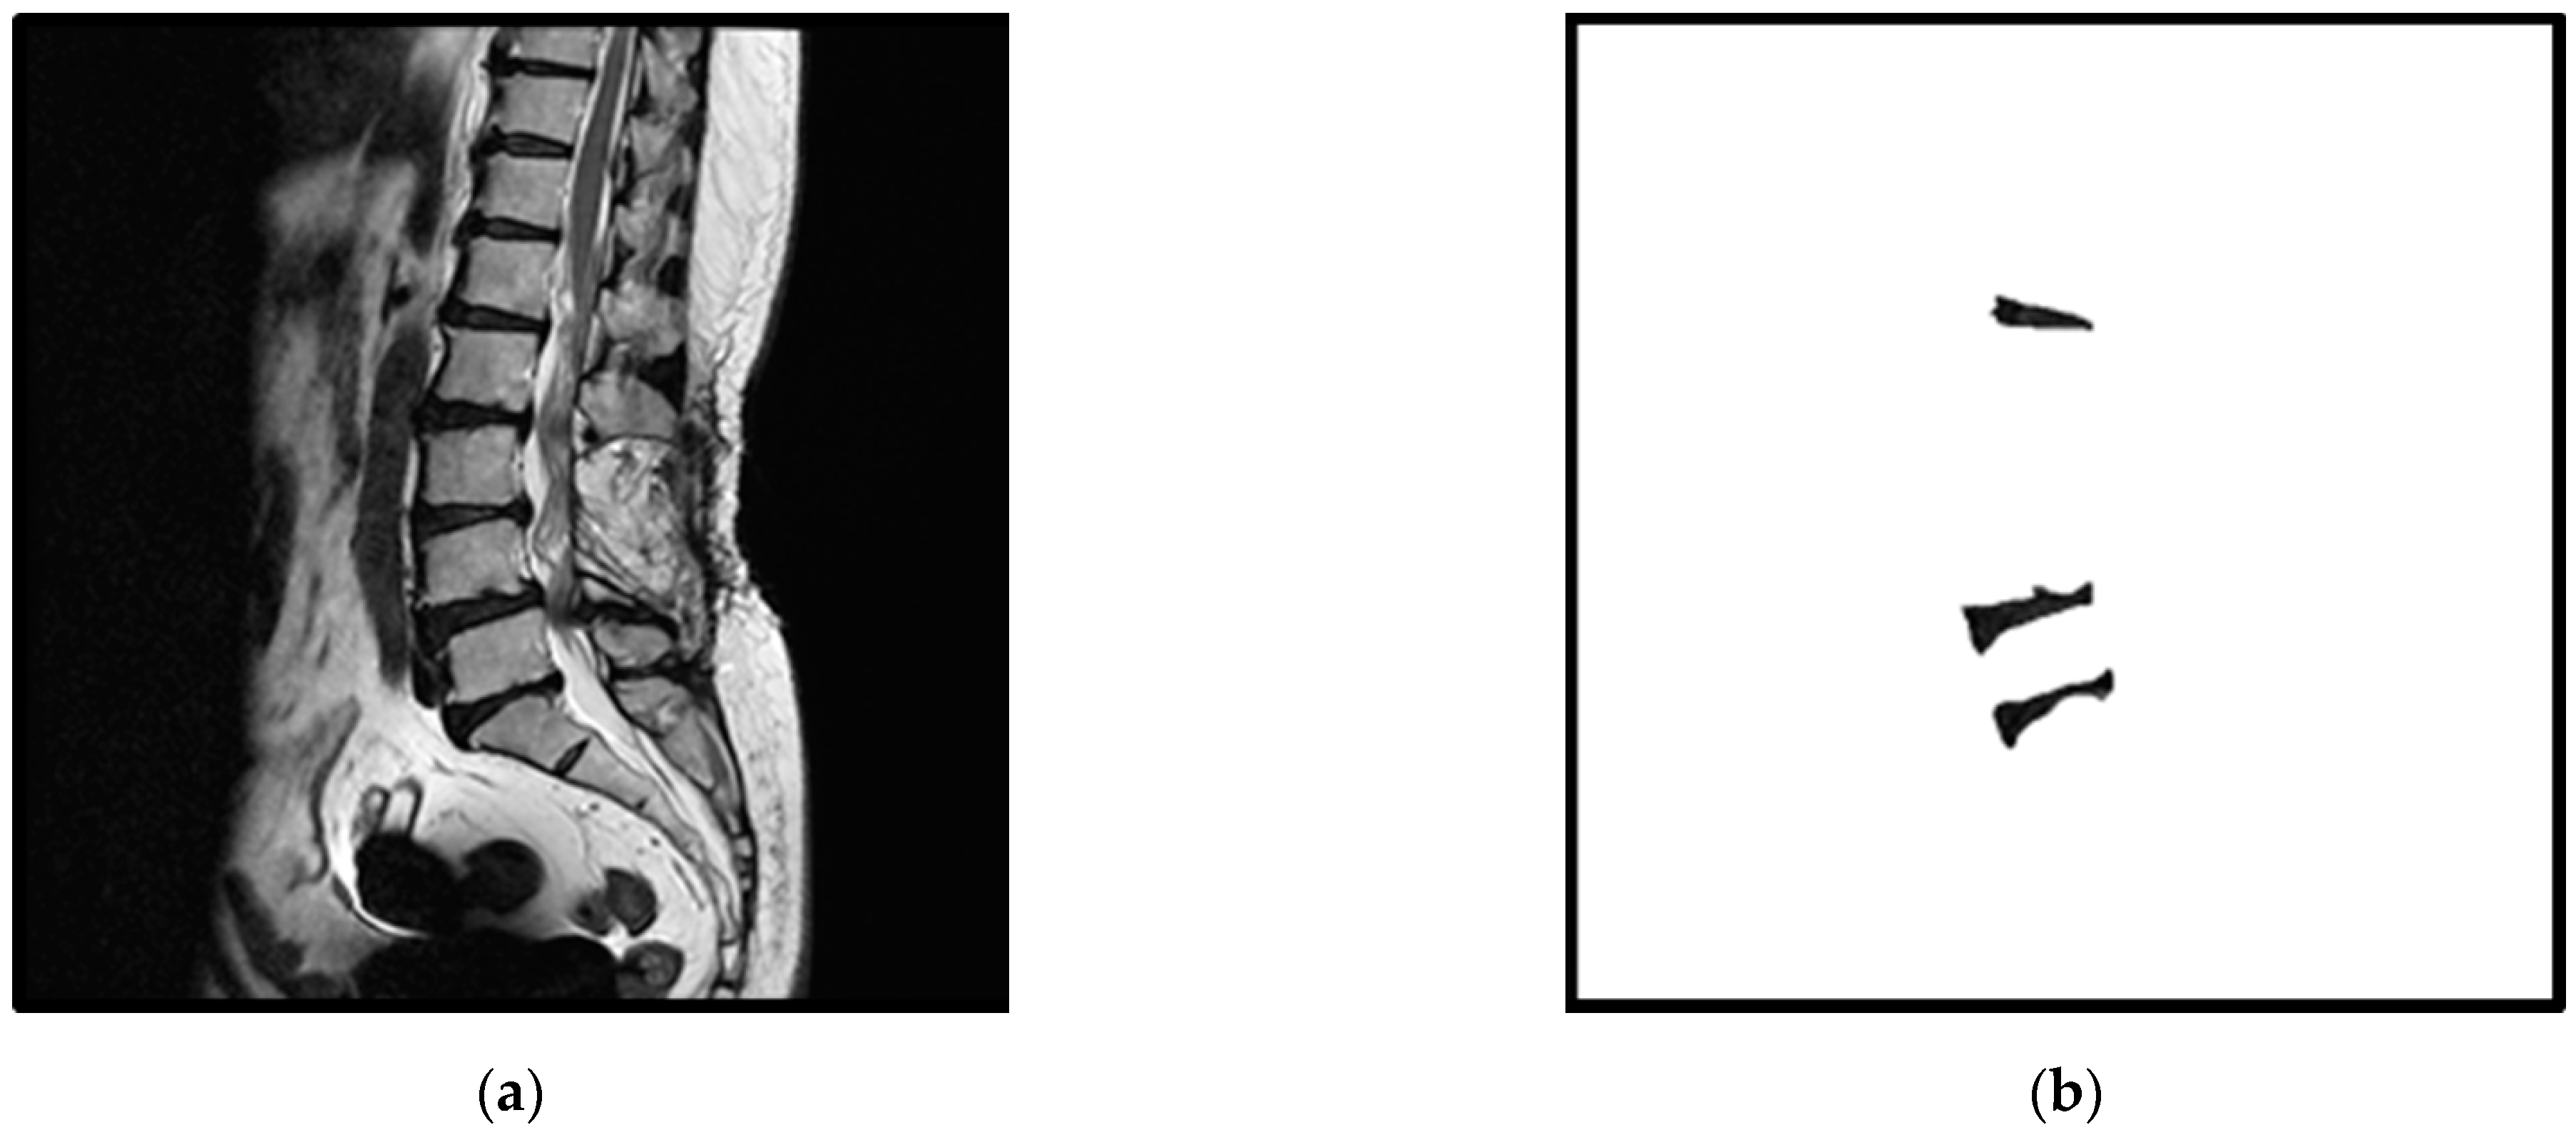

2. Materials

Figure 1. An example of an original spine MRI image and its corresponding standard masks of the three considered intervertebral discs: (a) the original spine MRI image; (b) the corresponding standard masks of the three intervertebral discs of (a).